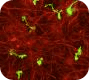

共培養モデル・神経炎症モデル (ミクログリア × アストロサイト × 神経細胞)

ミクログリア x アストロサイト x 神経細胞の3者共培養により、脳内環境を再現し、神経炎症カスケードの可視化や、Ca2+イメージングにて神経活動評価が可能です。

| 2023 | Society of Neuroscience | 2D and 3D tri-culture systems for investigation of cellular interaction among neurons, astrocytes, and microglia (Hayato Kobayashi, H. Kato, Setsu Endoh-Yamagami) | 脳は神経細胞とグリア細胞 (アストロサイト、ミクログリア、オリゴデンドロサイト) から構成され、脳機能や病態形成にはこれらの細胞の相互作用が重要である。本研究ではiPS細胞由来神経細胞、アストロサイト、ミクログリアの三者共培養系を構築し、神経炎症誘導によるミクログリアの形態変化や、ミクログリアとアストロサイトの細胞間相互作用を確認した。本培養系は、中枢神経系の細胞間相互作用の評価を可能とし、脳の本来の機能や病態形成の研究に大きく役立つことが期待できる。 | |

| 2023 | 第46回日本神経科学大会 | 2D and 3D tri-culture system composed of hiPSC derived neurons, astrocytes, and microglia (H. Kobayashi, H. Kato, S. Endoh Yamagami) |

神経変性疾患に深く関与する神経炎症において、ミクログリアの役割が注目されている。iPS細胞由来ミクログリア単独培養では、活性化状態に特徴的なアメボイド型を示したのに対し、アストロサイトや神経細胞と共培養することにより、ミクログリアが健常者のヒト脳内に近い多分岐型の形態を示した。また、炎症刺激であるLPSにより、3者共培養中のミクログリアが多分岐型からアメボイド型へと変化すること、さらには、LPS刺激による細胞の活性化が、ミクログリアからアストロサイトへ伝えられていくことを示した。神経炎症の理解に貢献することが期待できる。 | |